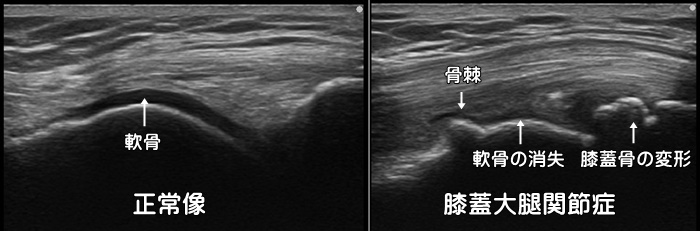

膝蓋大腿関節症

膝のお皿の骨(膝蓋骨)がその下にある大腿骨とすれる・ぶつかる事で痛みが発症します。ランニング・ロードバイク・階段昇降動作などで症状が発症します。最初は膝を屈伸する際の膝の皿の裏側の違和感や引っ掛かり感から始まり、進行すると痛みが出現します。